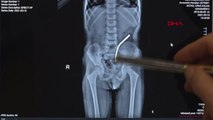

Kent merkezinde mıknatıslı boncuk bileklik yutan 5 yaşındaki kız çocuğunun bağırsağından 38 mıknatıs çıkartıldı.